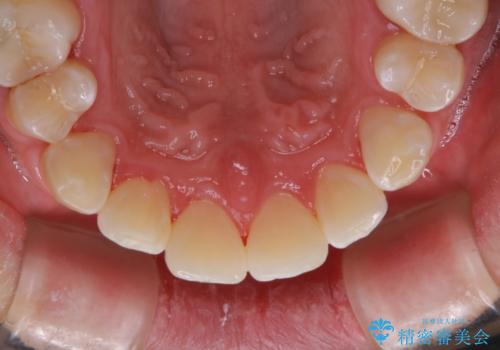

- 歯磨きをしても取れない汚れが気になるとのことで来院されました。PMTC60分コースを行いました。

歯周病やむし歯にならないように、定期的にプロフェッショナルケアを受け、お口の清潔を保つことが大切です。